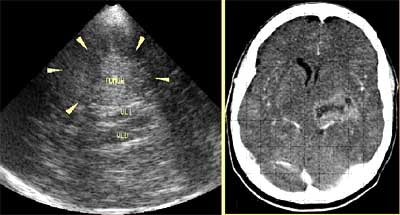

![]() |

| Depending on the region to be evaluated, transcranial Doppler ultrasound is performed by holding the transducer up to one of three windows in the head, including the orbital window (top) temporal window (left), and suboccipital window (bottom). Image courtesy of Dr. Orlando Valls Pérez. |